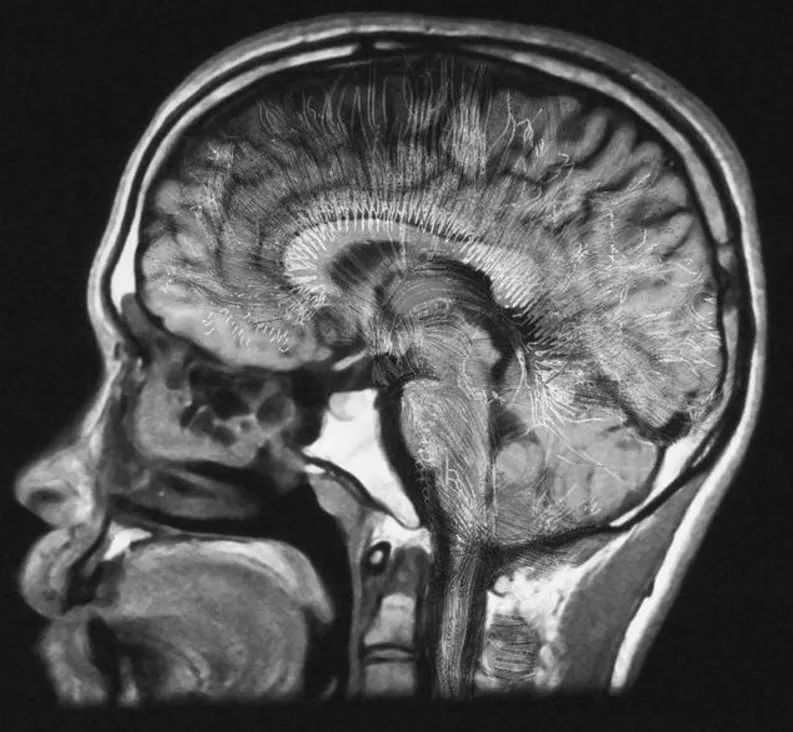

至于大脑如何维持我们的思想和意识,我们仍然知之甚少。不过随着成像技术的进步,在一定程度上揭示了大脑不同区域的神经元如何在不同的刺激下激发放电,就像圣诞树上的灯一样。

上面说的是理解神经元运行方式的简单部分。而困难的部分,则是了解活跃的神经元如何共同创造出「我们是谁」的感觉的。也就是说,生物电活动和血液流动,是如何转化为自我意识的。

有人提出,要了解大脑,必须沿着自下而上道路:从单个神经元到突触链接,再到在它们之间流动的神经递质,再到神经元簇和大脑回路。